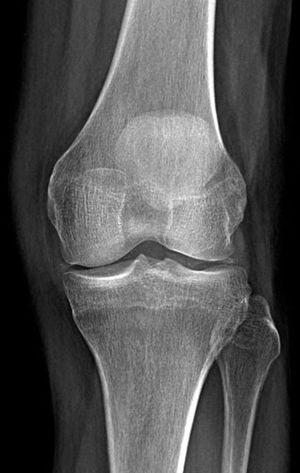

65 yr old male presents to his family Dr with left knee pain and morning stiffness for the past year that has progressively worsened. A radiograph of the left knee is ordered for the further evaluation. *What is the Diagnosis?*

Could be Osteoarthritis with the non uniform joint space narrowing and eburnation (bony sclerosis) margin of the bone is whiter there could be spiking of tibial condyle. Diagnosed by joint pain, morning stiffness, absence of constitutional symptoms and on examination there will be increased bony prominence at the joint margins anf atrophy of surrounding muscle, there could be grating sensation with tenderness over the joint line and joint movement limitation

It may be a osteo arthritis x ray denotes joint narrowing spaces with osteophytic changes pls clarify once signs,symptoms and examination which related to osteo arthritis